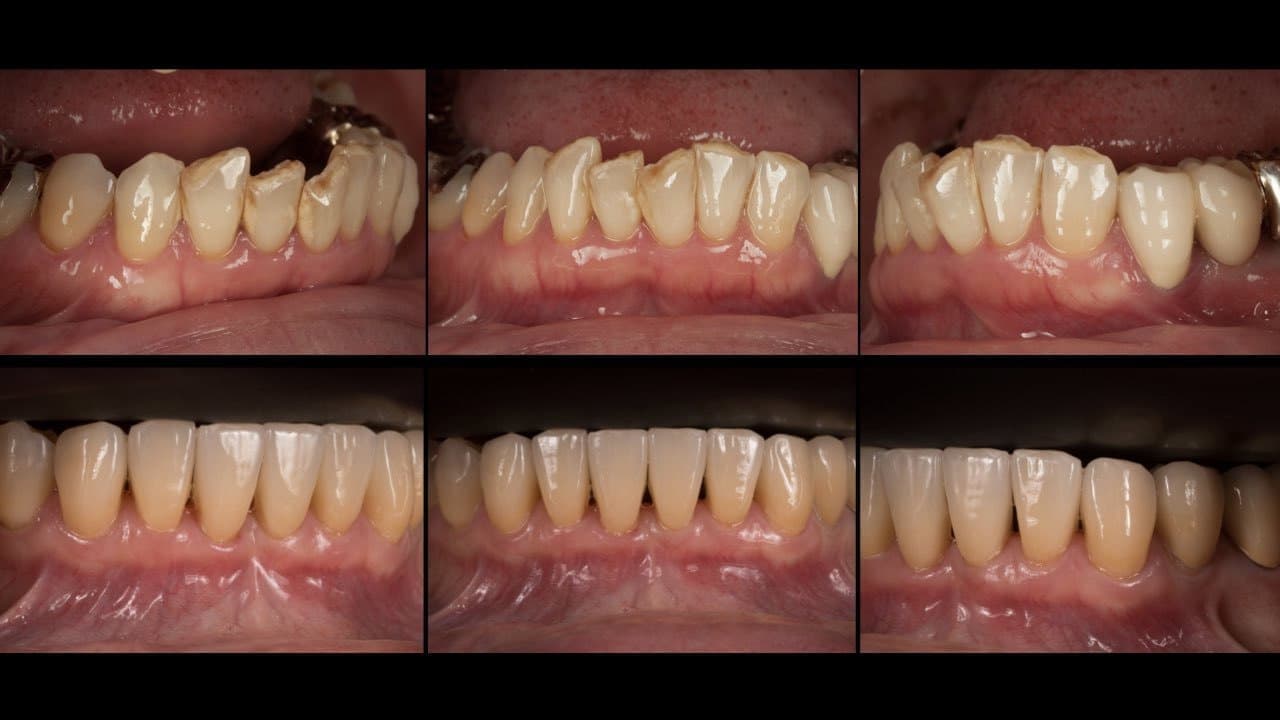

出来る限り歯を抜かない

一般的な歯周病(慢性歯周炎)に関する治療法は、ほぼ確立されています。私達は、出来る限り歯を抜かずに歯周病治療する事で歯を温存できるよう日々努力しています。

適切な治療を行えば、健康な口腔内を実現できます